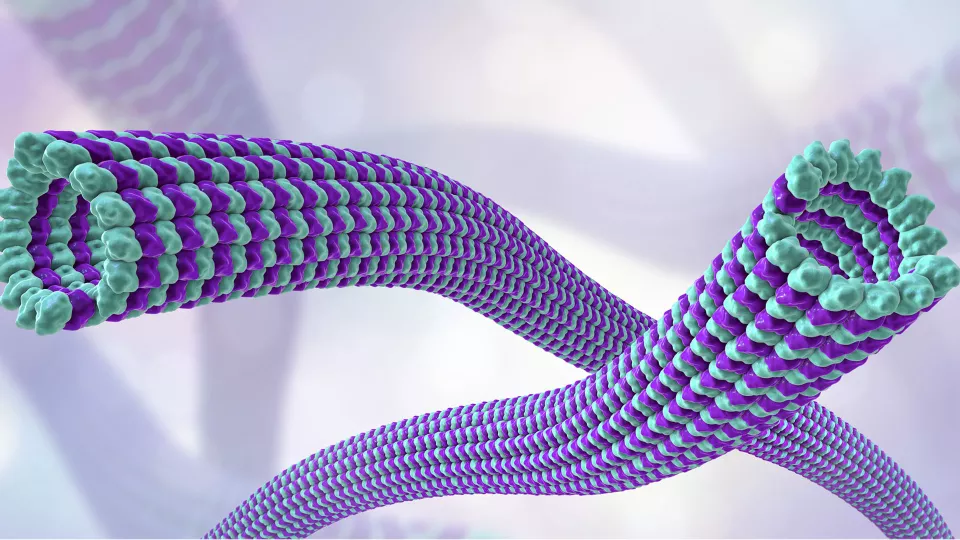

Study to Characterize M. tuberculosis’ Pathogenic Proteins and How They Cause Disease